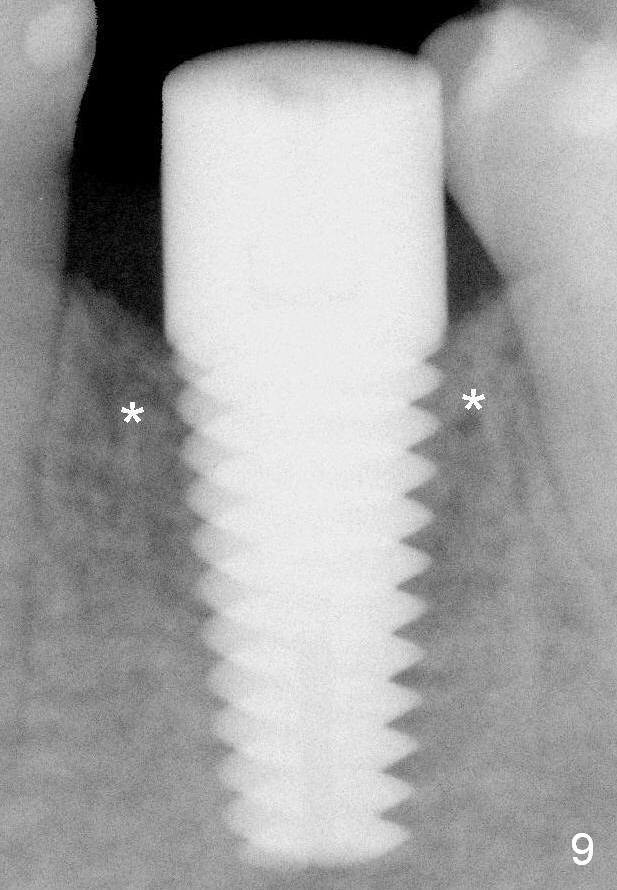

Fig.9 (6 months postop): Bone density around the coronal aspect of the implant increases (*). Apical resorption occurs.